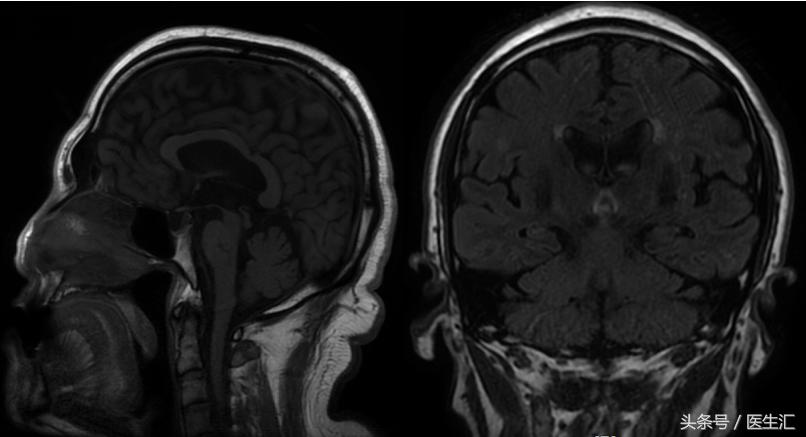

影像检查

诊断:

进行性核上性麻痹-帕金森型